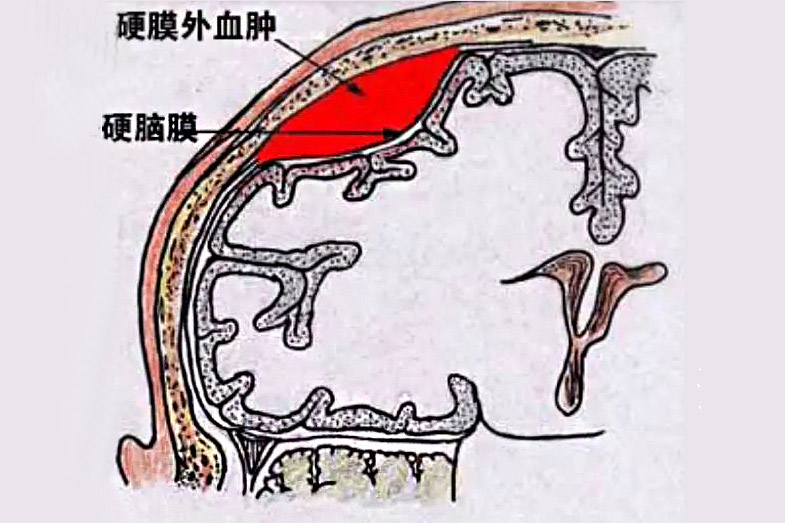

①同一部位不同类型的多发血肿

多为对冲性脑挫裂伤伴急性硬脑膜下血肿及脑内血肿;或着力部位硬膜外血肿伴局部硬脑膜下及/或脑内血肿。

见于着力部位硬脑膜外血肿及/或脑内血肿伴对冲部位硬脑膜下及脑内血肿。有时枕部减速性损伤,引起枕骨骨折,可致颅后窝硬脑膜外血肿,伴对冲部位硬膜下及/或脑内血肿。此类血肿临床表现常较严重,病人伤后多持续昏迷或意识障碍变化急促,容易早期出现天幕切迹疝及双侧锥体束受损征。

1)同一部位不同类型血肿的清除

较常见的是额颞前份对冲性脑挫裂伤,急性硬脑膜下伴脑内血肿,属混合性同一部位的血肿,往往彼此相连,故可在同一手术野内一并清除,偶尔需行脑穿刺始能发现;其次是硬脑膜外血肿伴发硬膜下或局部脑内血肿,可疑时必须切开硬脑膜探查硬膜下或行脑穿刺,证实后予以清除。